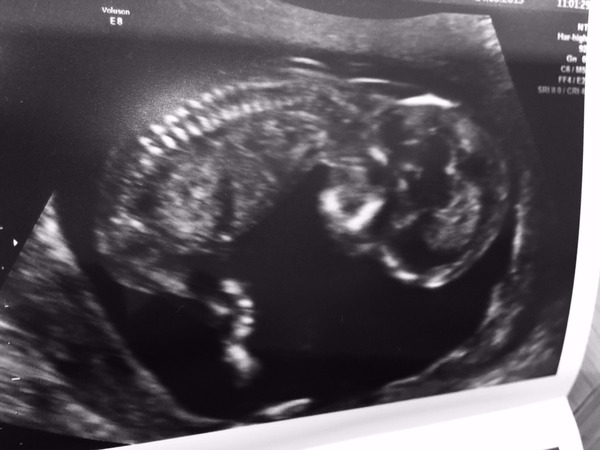

I'm back from scan, and all good, one real live baby, date put forward slightly to 19th Nov so I'm 13 weeks exactly. Downs risk 1:5000ish so v happy with that given I'm 36.

Hooray! Baby was so sweet, long legs sticking right out. Can't wait to find out if it's DS3 for us...which I'm sure it will be, I don't think we make girls!

Congrats Dixie great scan picture!